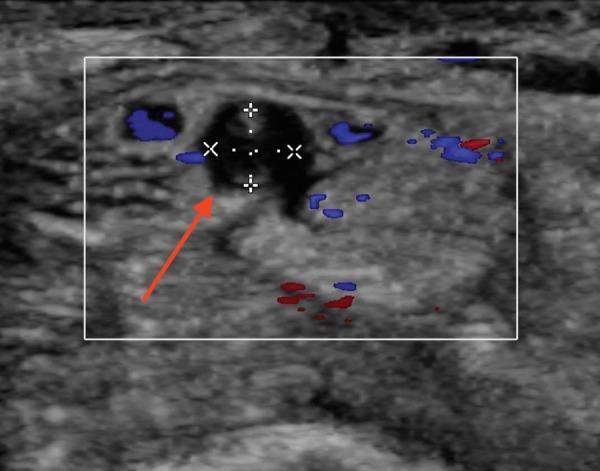

: Carpal tunnel syndrome (CTS) is a sporadic event with compression of the median nerve (MN). Persistent median artery (PMA) thrombosis is an exceptionally rare cause of CTS. : 38-year-old male presented with acute on subacute right wrist pain with positive Tinel's sign. An ultrasound and computed angiography study confirmed a PMA with thrombosis. The patient was treated with intravenous heparin then discharged home on enoxaparin and warfarin crossover. : PMA can lead to CTS by compression from the adjacent median nerve. Thrombosis of the PMA can also lead to CTS. Surgical intervention is needed in cases of severe CTS. Carpal tunnel release is usually successful. Excision of the PMA can risk vascular compromise of the digits. Ultrasound is excellent for detecting rare causes of CTS. : Ultrasound examination for CTS should include search for PMA and associated anatomical variations.

腕管综合征(CTS)是一种因正中神经(MN)受压引起的散发性疾病。持续性正中动脉(PMA)血栓形成是CTS极为罕见的病因。一名38岁男性因亚急性右腕疼痛伴Tinel征阳性就诊。超声和计算机血管造影检查证实存在PMA伴血栓形成。患者先接受静脉肝素治疗,然后出院时改用依诺肝素和华法林交叉治疗。PMA可通过对相邻正中神经的压迫导致CTS。PMA血栓形成也可导致CTS。严重CTS病例需要手术干预。腕管松解术通常很成功。切除PMA可能会有手指血管受损的风险。超声对于检测CTS的罕见病因非常有效。对于CTS的超声检查应包括寻找PMA及相关解剖变异。